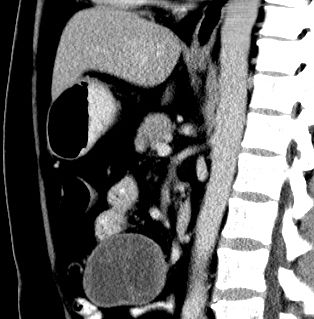

男,48岁,间断性下腹不适1年。

手术探查

:距回盲部28厘米处肠系膜根部可见5*7cm左右包块,质中等硬度,活动度尚可,肝、胆、胰、脾肾未见明显异常。

病理

:(腹腔)

神经鞘瘤

,伴出血、坏死及囊性变,伴淋巴结反应性增生。

免疫组化结果

:sma(-), desmin(-), cd117(-), s-100(+++), nf(-),vimentin(+++).